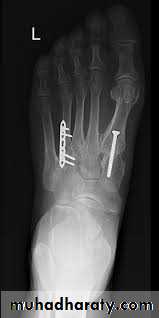

A condition characterized by disruption between the articulation of the medial cuneiform and base of the second metatarsal

unifying factor is disruption of the TMT joint complex

injuries can range from mild sprains to severe dislocations

may take form of purely ligamentous injuries or fracture-dislocations

ligamentous vs. bony injury pattern has treatment implications

Lisfranc Injury (Tarsometatarsal fracture-dislocation